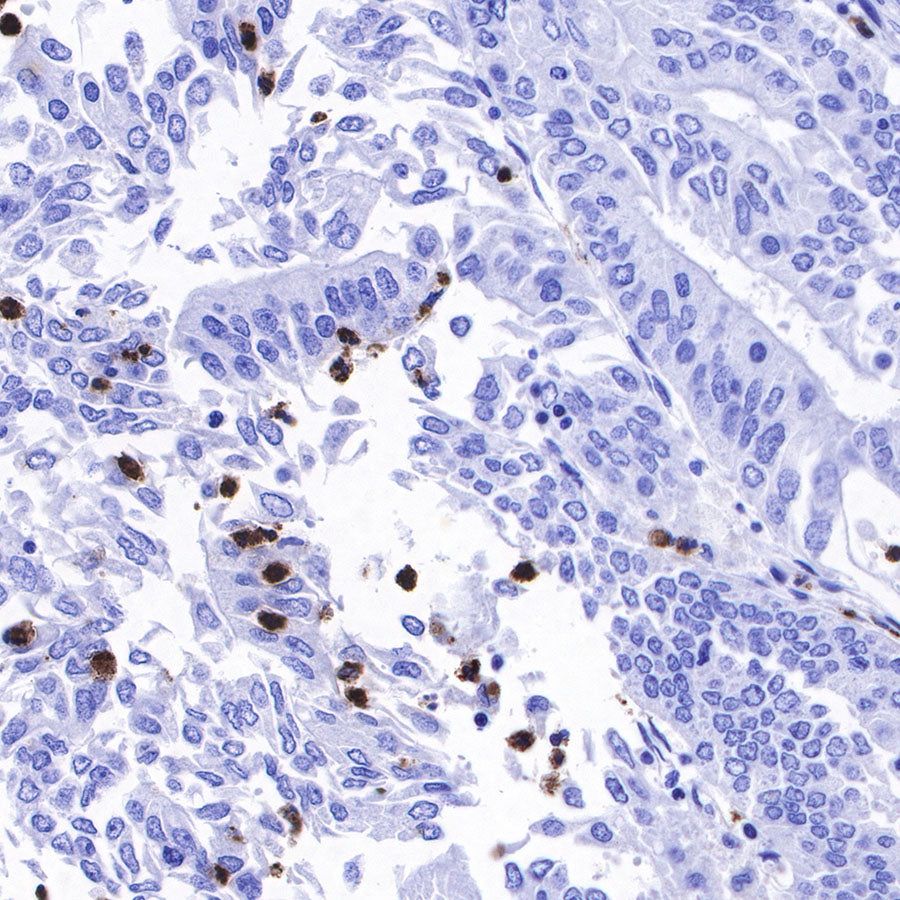

IHC shows positive staining in paraffin-embedded human lung squamous cell carcinoma. Anti-Lysozyme antibody was used at 1/100 dilution, followed by a HRP Polymer for Mouse & Rabbit IgG (ready to use). Counterstained with hematoxylin. Heat mediated antigen retrieval with Tris/EDTA buffer pH9.0 was performed before commencing with IHC staining protocol.